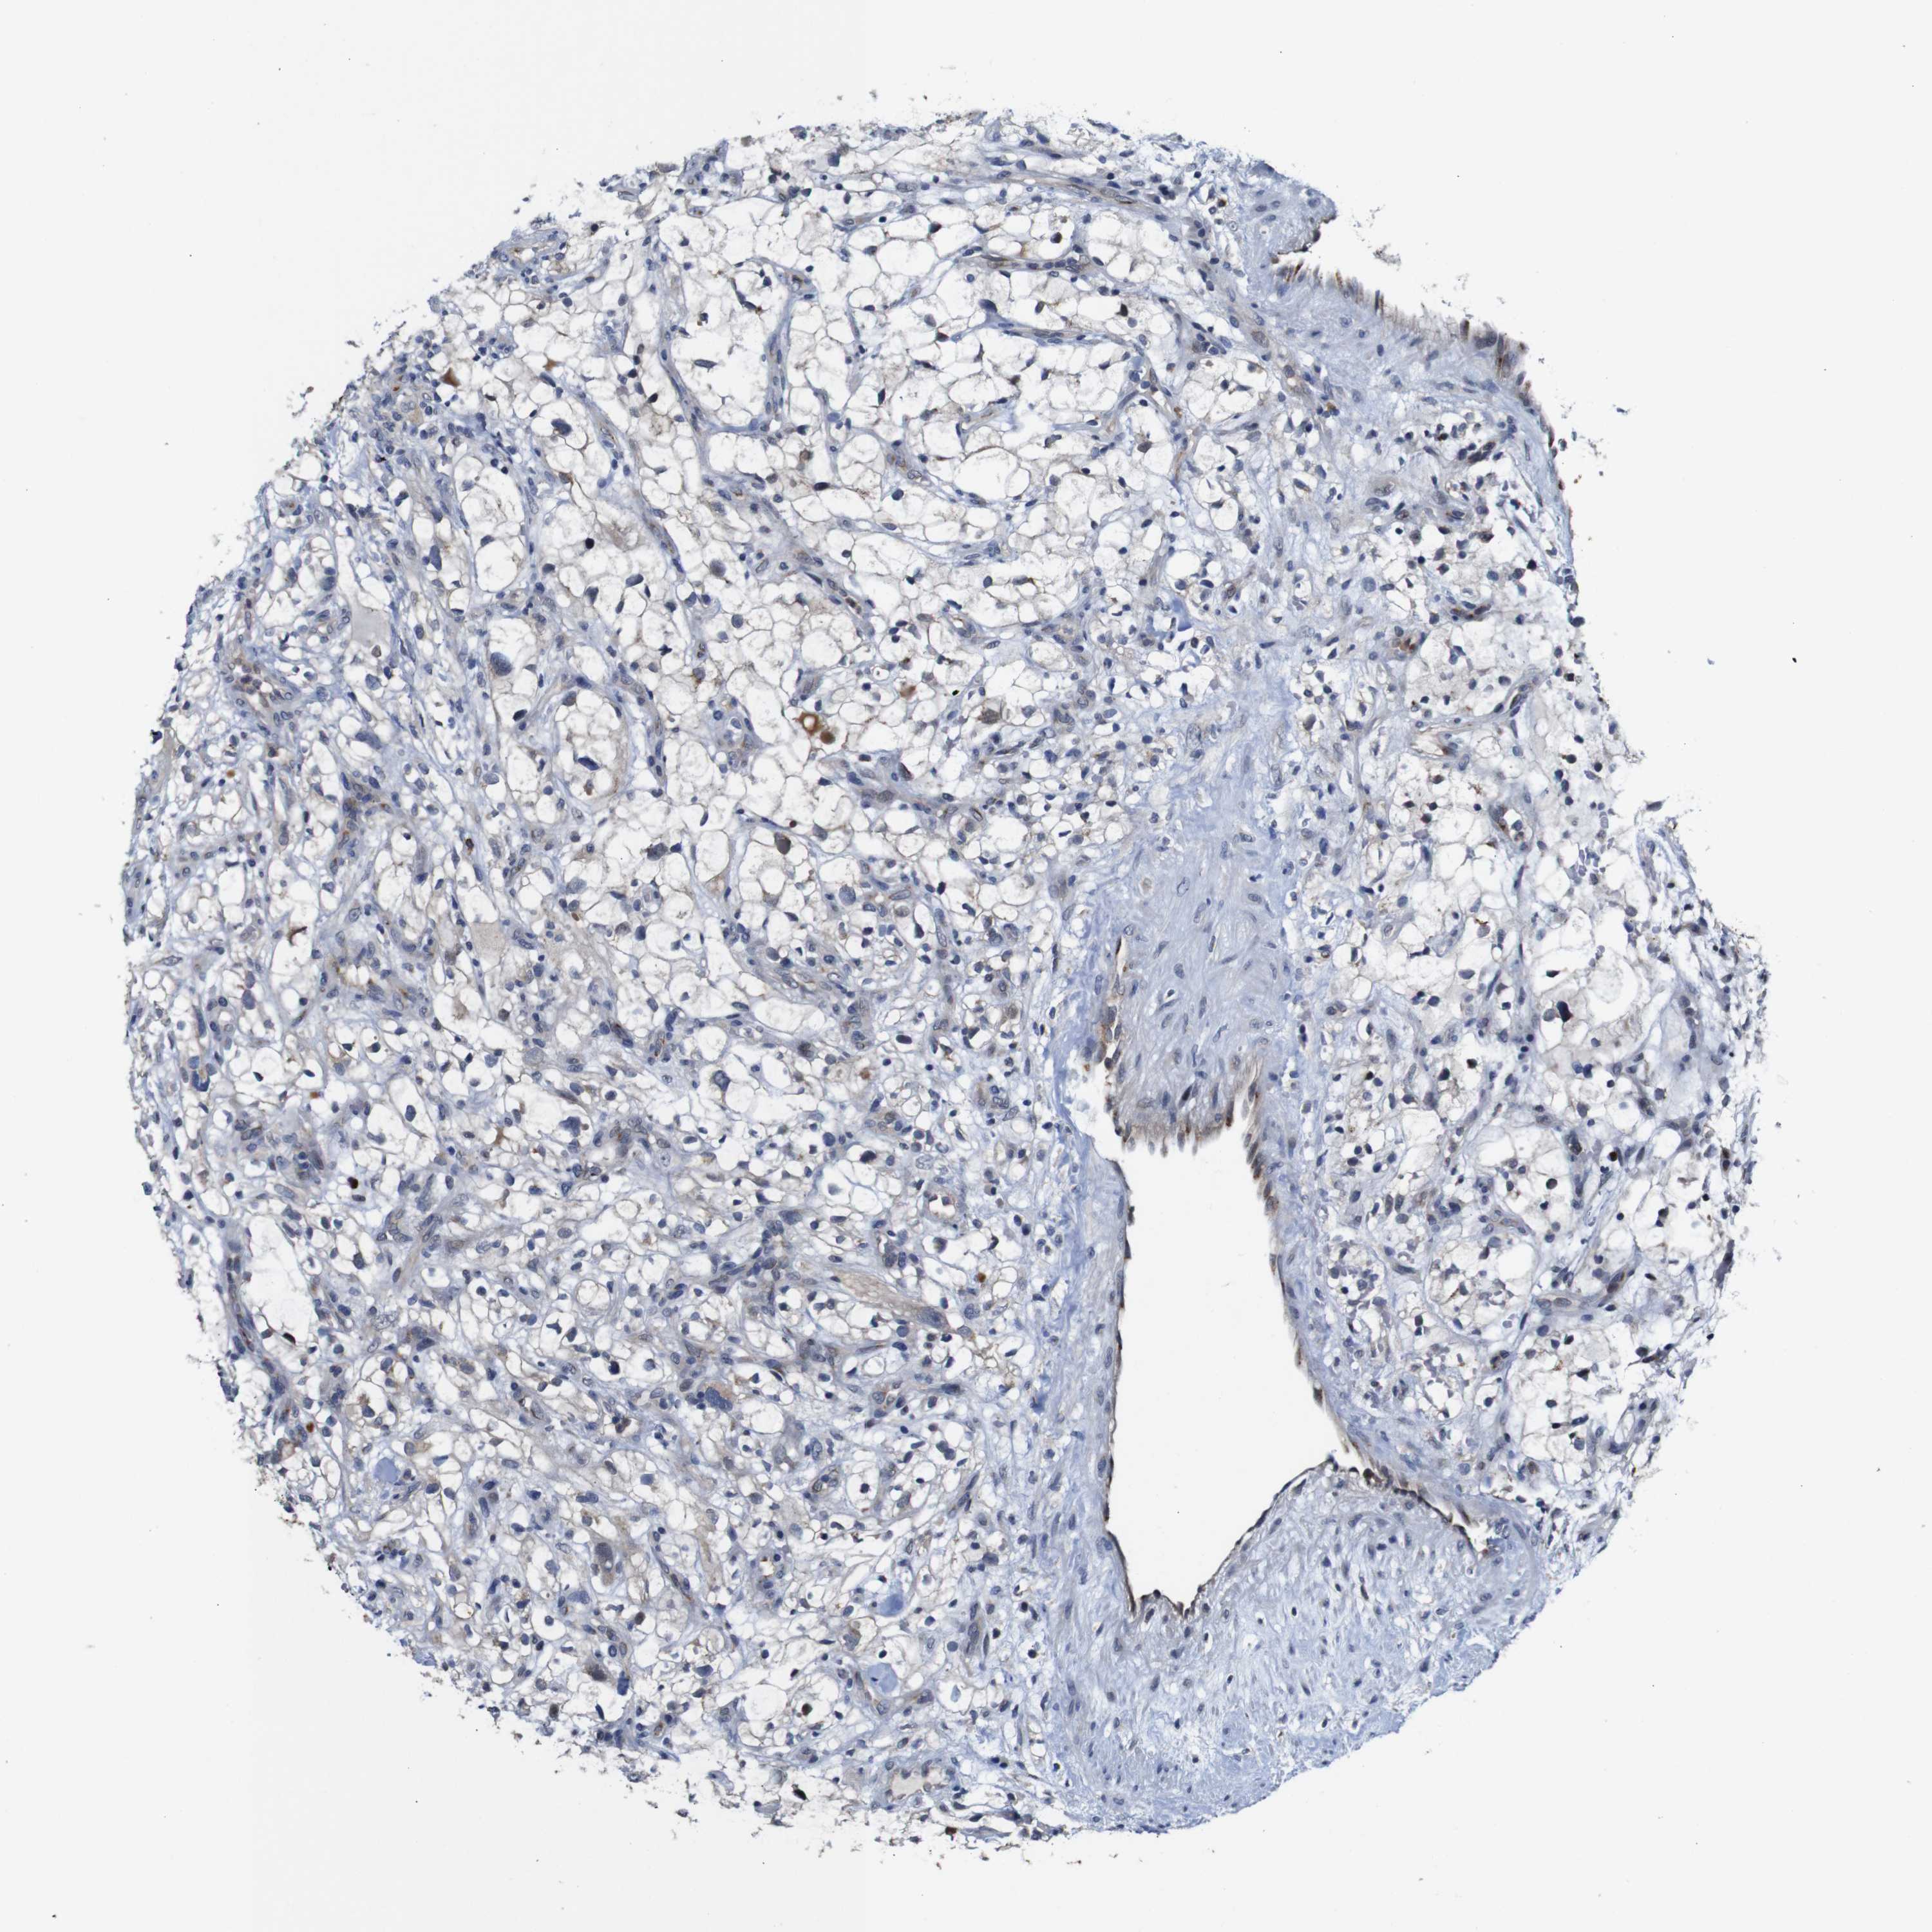

CANCER RENAL CANCER Show tissue menu

KICH TCGA KIRC TCGA KIRC VALIDATION KIRP TCGA PROTEIN RCC CPTAC PROTEIN EXPRESSION

Renal cancer

Kidney chromophobe